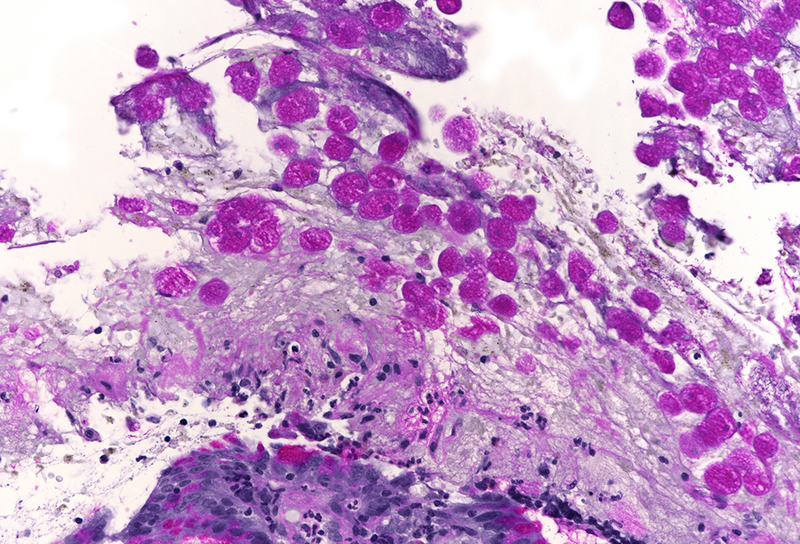

Histology revealed colonic mucosa with preserved architecture. Multiple erosions, crypts with degenerative features and increase of the inflammatory cell infiltrate in the lamina propria, especially granulocytes, were observed (PANEL A-B). On the luminal surface, accompanied by fibrin and debris, multiple organisms with roundish shape, foamy cytoplasm and round, pale and eccentric nuclei were found; some of those have erythrocytes engulfed in their cytoplasm (PANEL C-D); periodic acid-Shiff (PAS) stain highlights these organisms (PANEL E-F), which qualify for diagnosis of amoebiasis.

Histologically, initial lesions show a mild neutrophilic infiltrate, with numerous organisms present at the luminal surface associated with detritus. In advanced disease, ulcers are often deep, extending into the submucosa, sometimes with invasive amoebae within the bowel wall. Entamoeba histolytica has a roundish shape, with foamy cytoplasm and round, pale and eccentric nuclei with an open nuclear chromatin pattern. Within the inflammatory exudate, they may be difficult to distinguish from macrophages; in these cases, histochemical and immunohistochemical stains may be performed: amoebae are trichrome- and PAS-positive and macrophages stain with CD68. It is noteworthy the presence of ingested erythrocytes as pathognomonic feature of this parasite.